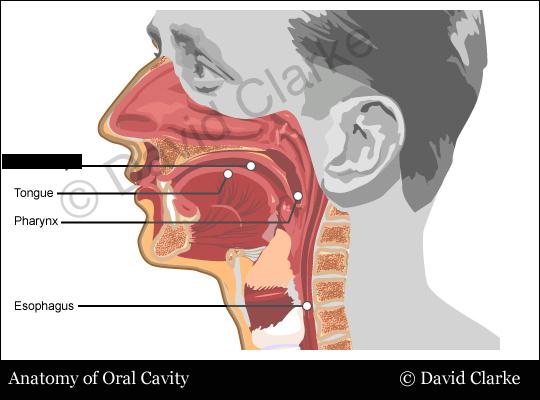

Esophagus

Hard/soft palate

Inferior/middle/superior concha (s.) conchae (pl.)

Nares

Nasal Cavity

Nasal septum

Naso/oro/laryngo-phraynx

Oral Cavity

Tongue

Uvula

Vestibule (of nasal cavity)

Vocal folds (=vocal cords)